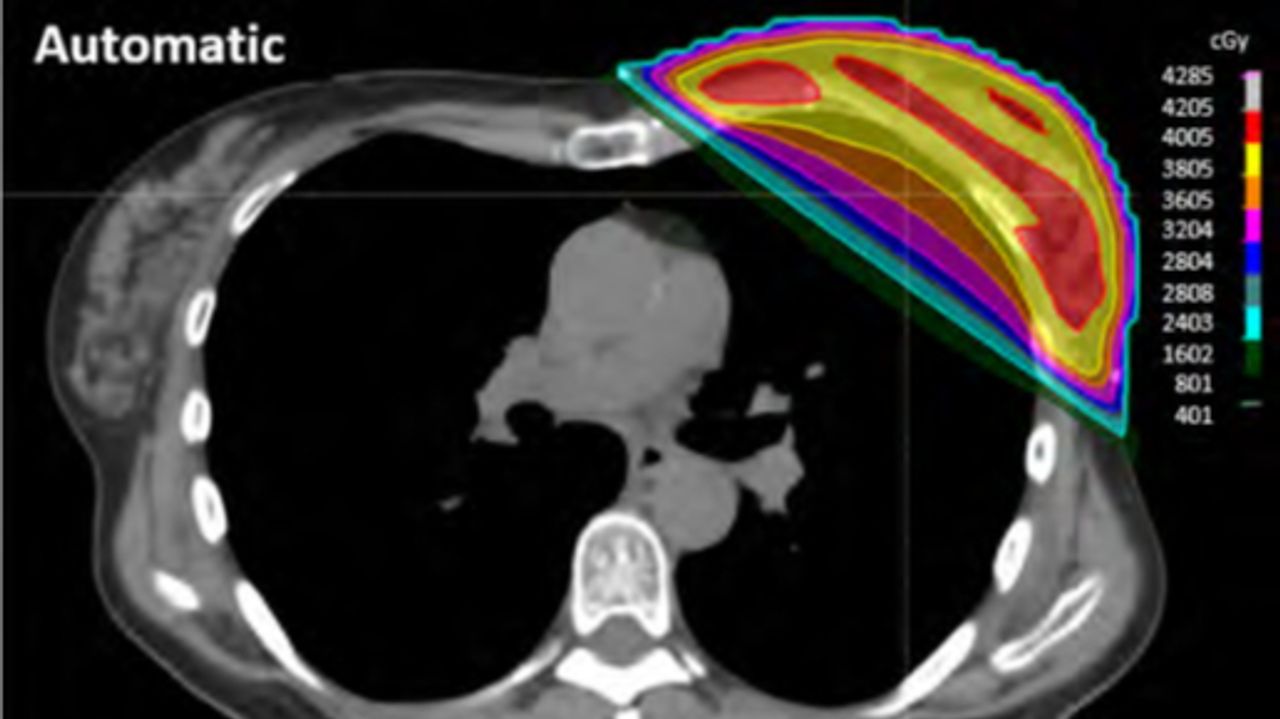

"Vanuit welke hoek moeten we de patiënt bestralen? Hoeveel dosis moet die patiënt in de borst krijgen om te zorgen dat het tumorweefsel dat is overgebleven na de operatie daadwerkelijk doodgaat?" Het zijn allemaal vragen waarop de computer antwoord kan geven.

"Bestraling is nou eenmaal schadelijk. We willen daarom andere organen die eromheen liggen niet al te veel beschadigen. Constant wordt er een afweging gemaakt. Ik wil hier zoveel dosis in de borst geven, maar ik wil ook niet dat er te veel in het hart of een long komt. De afweging moest tot nu toe met de hand gemaakt worden. Nu kan het automatisch."